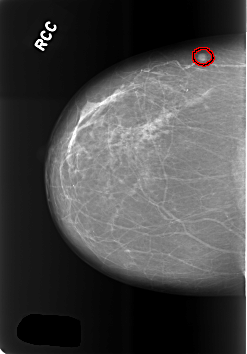

C_0485_1.RIGHT_CC

RIGHT_CC LINES 5664 PIXELS_PER_LINE 3944 BITS_PER_PIXEL 12 RESOLUTION 50 OVERLAY

FILE: C_0485_1.RIGHT_CC.OVERLAY

TOTAL_ABNORMALITIES 1

ABNORMALITY 1

LESION_TYPE MASS SHAPE ROUND MARGINS CIRCUMSCRIBED

ASSESSMENT 3

SUBTLETY 5

PATHOLOGY BENIGN

TOTAL_OUTLINES 1

BOUNDARY